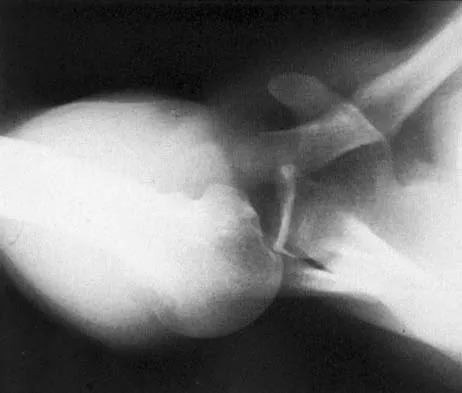

Figure 17 shows the radiograph of a 25-year-old professional football player who has superior shoulder pain that prevents him from sports participation. History reveals that he sustained a shoulder injury that was treated with closed reduction and temporary pinning 3 years ago. The best course of action should be